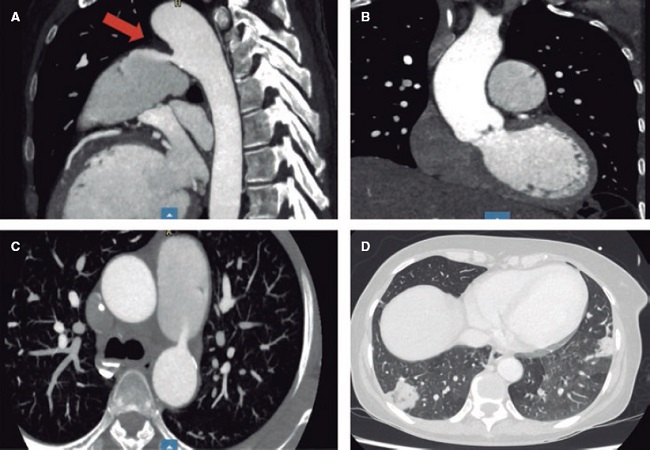

Mujer de 52 años que ingresó por ictus isquémico tratado con trombectomía mecánica. Refería fiebre durante el mes previo y en la exploración destacaba un soplo continuo sistólico-diastólico. Se le realizó un ecocardiograma que evidenció ductus arterioso persistente de 7 × 5 mm con repercusión hemodinámica (sobrecarga de cavidades izquierdas) (figura 1A,B, flecha; vídeos 1 y 2 del material https://doi.org/10.24875/RECIC.M23000427adicional). Se detectó además una verruga sobre la válvula aórtica, con ligera insuficiencia. En hemocultivos se aisló Streptococcus sanguinis. La angiografía de tórax por tomografía computarizada, además de caracterizar el ductus, mostró una vegetación sobre el tronco pulmonar con embolias sépticas pulmonares (figura 2A-D, flecha). Se pautó tratamiento antibiótico por 4 semanas. Ante el empeoramiento ecocardiográfico (crecimiento de vegetación y progresión de la insuficiencia) (figura 1C,D; vídeos 3 y 4 del material adicional https://doi.org/10.24875/RECIC.M23000427adicional) se decidió intervenir quirúrgicamente para sustituir la válvula aórtica por una prótesis mecánica y cerrar el ductus con parche.